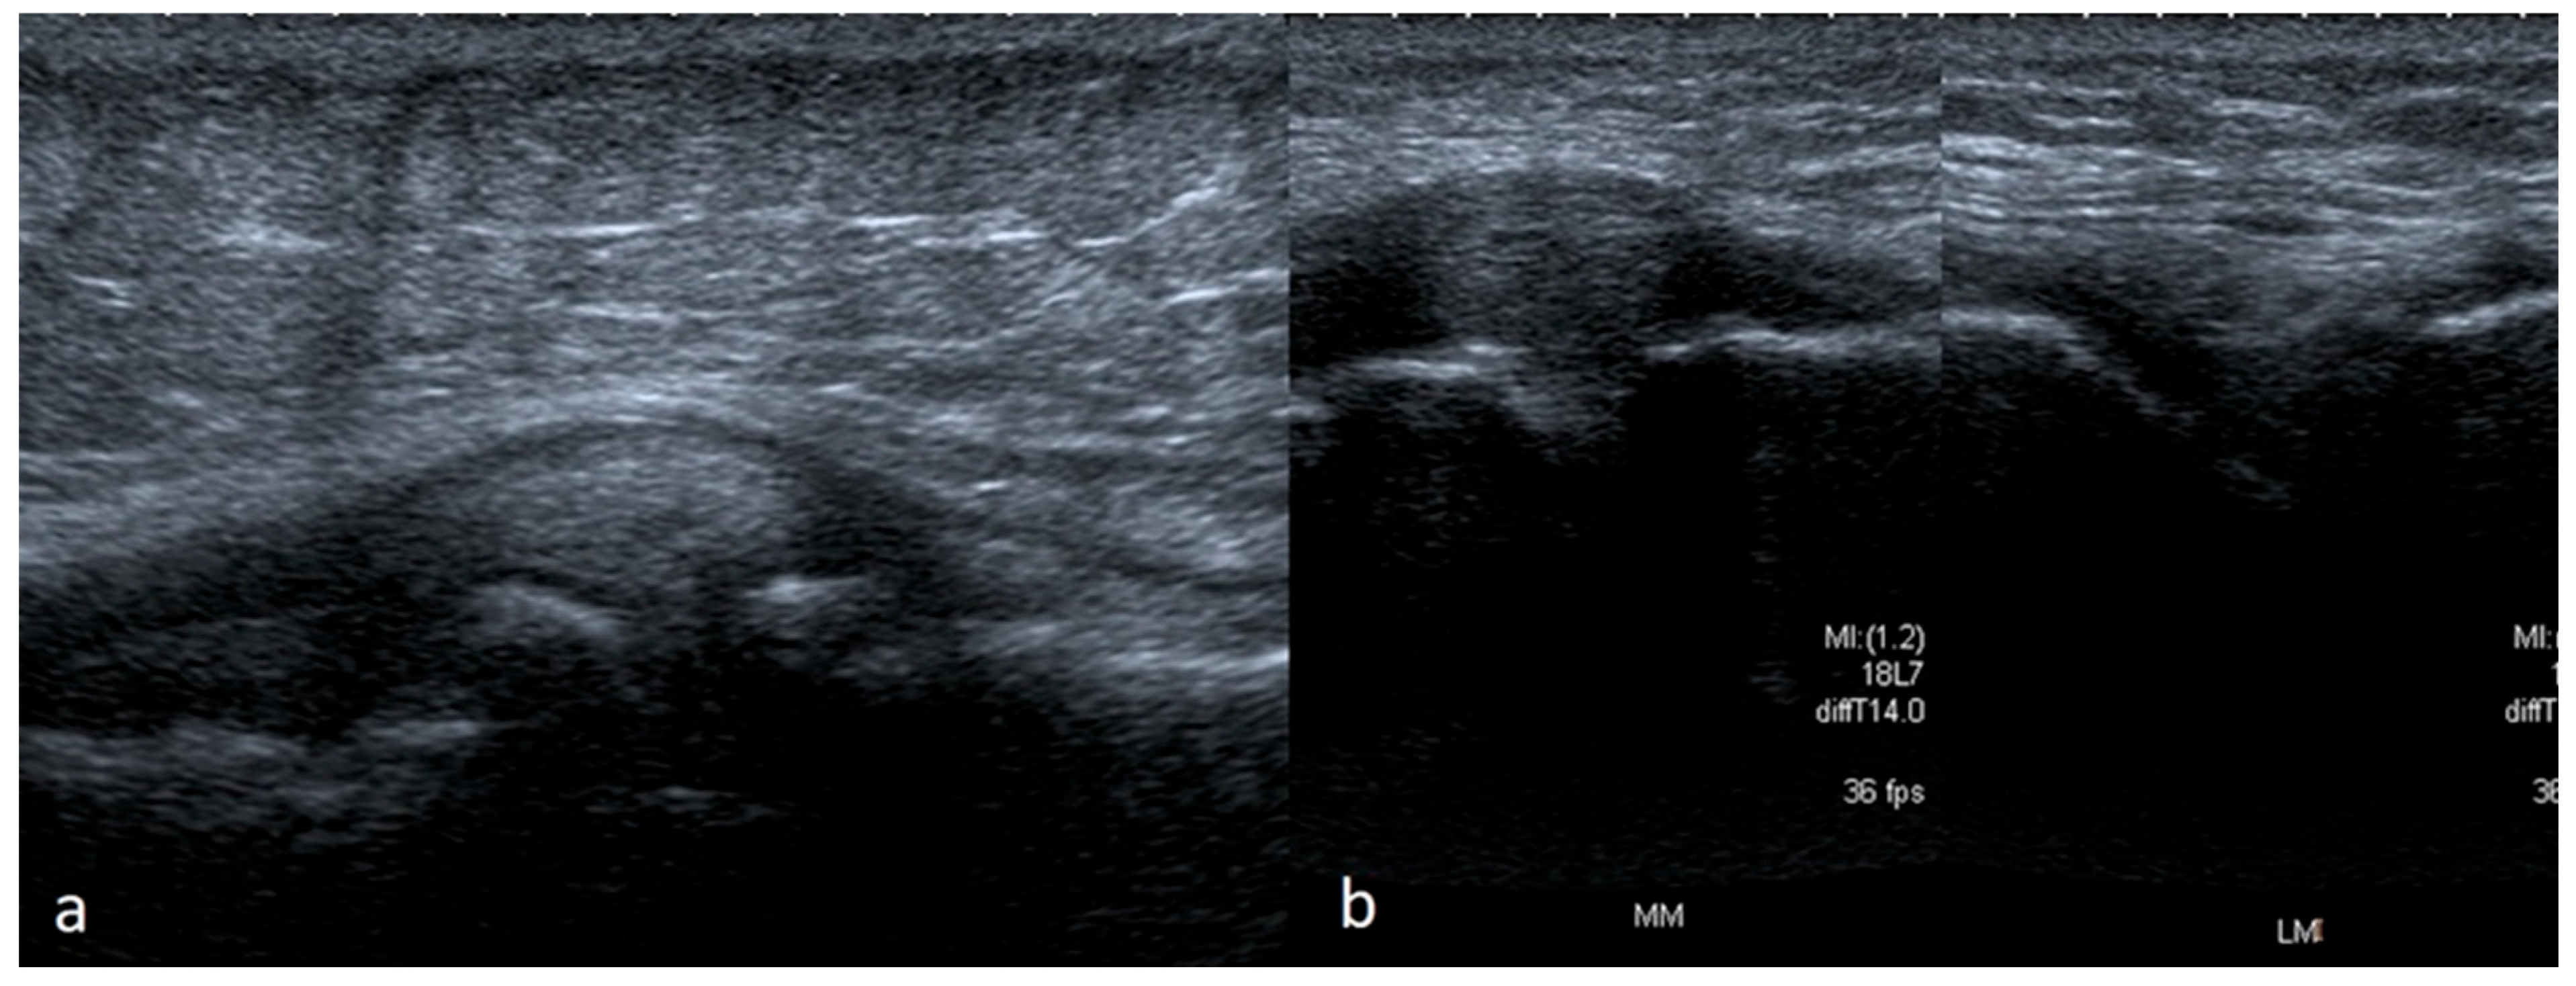

3.1.1. Meniscus Tears

3.1.2. Meniscus Cysts

3.1.3. Bucket-Handle Tears

3.1.4. Meniscal Flap Tears

3.1.5. Degenerative Changes of Menisci